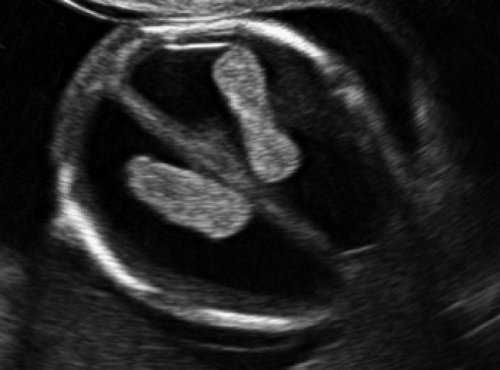

Анализ сохраненных трехмерных изображений позволил получить более детальные характеристики структур мозга плодов с РЭС. На среднесагиттальном срезе в наблюдениях 1, 2 и 4 (в наблюдении 3 получить качественно этот срез не удалось) отмечено наличие атипичной полукруглой формы шатра (fastigium) 4-го желудочка, гипоэхогенная структура мозжечка с контрастирующим наружным контуром (рис. 3). При этом в первых трех наблюдениях отмечено полное отсутствие структур червя, тогда как в наблюдении 4 по контуру 4-го желудочка выявлены гиперэхогенные структуры, расцененные как передние отделы червя. Наличие передних отделов червя отражает и ряд послойных срезов в режиме TUI (рис. 4). У плода в наблюдении 4 также обращает на себя внимание относительное расширение надмозжечковой цистерны, с линейными структурами, при нормальной ориентации намета мозжечка (рис. 4).

На эхограмме: М - мозжечок, 4v - четвертый желудочек, короткие стрелки - фрагменты червя.

При частичном РЭС в наблюдении 4 картины желудочковой системы (затылочные рога боковых желудочков - 7 и 7,9 мм, 3-й желудочек - до 2 мм), комплекса "полость прозрачной перегородки (ППП - 3,4 мм) - мозолистое тело (20,8 мм)", борозд мозга (глубина сильвиевой борозды - 7 мм), длины крыши четверохолмия (8,3 мм), водопровода, передне-задних диаметров мезенцефалона (11 мм) и моста (7,9 мм) соответствовали норме (рис. 6).

На эхограмме: М - мозжечок, Ц - цистерна, стрелка короткая - намет мозжечка, стрелка длинная - 4-й желудочек.